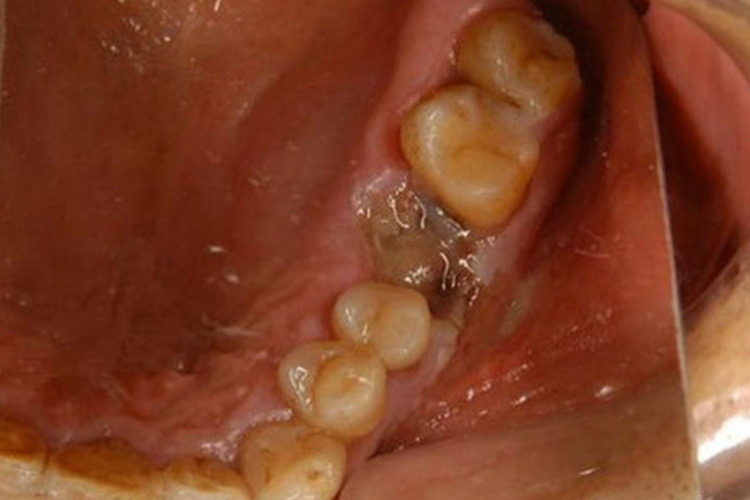

干槽症是拔牙创口急性感染的一种类型, 以下颌后牙多见, 特别是在下颌阻生第三磨牙拔除术后。在正常情况下,即使是翻瓣去骨拔牙术,正常牙洞创口的疼痛2~3天后会逐渐消失。如果拔牙2~3天后出现剧烈的疼痛,疼痛向下颌下区或头顶部放射,用一般的止痛药物不能缓解,则可能发生了干槽症。

临床检查可见牙槽窝内空虚,或有腐败变性的血凝块,呈灰白色。在牙槽窝壁覆盖的坏死物有恶臭,用探针可直接触及骨面并有锐痛。颌面部无明显肿胀,张口无明显受限,下颌下可有淋巴结肿大、压痛。组织病理表现为牙槽窝骨壁的浅层骨炎或轻微的局限型骨髓炎。